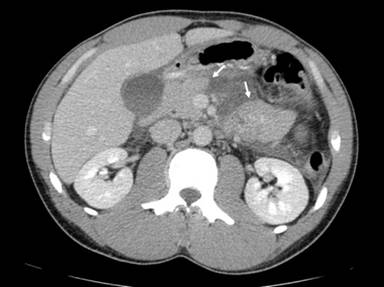

Computed tomography of abdomen and pelvis demonstrated a transection at the neck of the pancreas with large amounts of high attenuation free fluid and no other injuries (Figures 1 and 2). The patient was taken to the operating room for emergent laparotomy. Upon entering the abdomen, an extensive inflammatory and hemorrhagic reaction was encountered which encompassed the entire omentum and lesser sac, obscuring normal anatomy. It was deemed impossible to explore the site of injury through a direct anterior approach. Therefore the spleen and tail of the pancreas were mobilized anteromedially, exposing the site of transection to the left of the superior mesenteric vessels along with extensive devitalization of the distal remnant. The major pancreatic duct could not be visualized. Albumin-glutaraldehyde surgical adhesive (BioGlue®; Cryolife Inc., Kennesaw GA, USA) was applied to the cut surface of the proximal stump and distal pancreatectomy and splenectomy were completed. Two closed suction drains were placed.

Figure 1. Contrast-enhanced CT scan of abdomen and pelvis demonstrating transection at the junction of the pancreatic neck and body (arrows). |